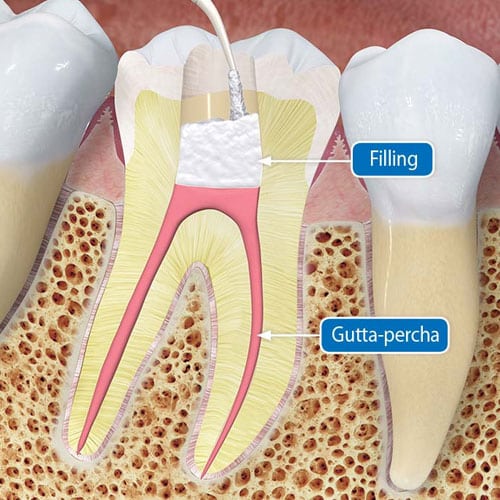

The pulp is the living tissue of the tooth with blood supply and nerve supply. Once dental caries (decay ) involves the pulp, the pulp gets infected causing pain. The aim of the root canal treatment is to remove the infected pulp. This is done by removing the infected pulp with files in the pulp chamber and cleaning and shaping the root canals and sealing the canal with a filling material. At Anbu Dental Clinic, we provide the best root canal treatment at an economical cost in whole Madurai city. “PRESERVING YOUR TOOTH FOR YOUR FUTURE”.

Each tooth has a soft tissue – the pulp which nourishes the tooth. Because of deep decay, injury, or gum disease, the pulp tissue in your tooth has become inflamed or infected. In any other part of your body, if a similar tissue becomes diseased, the body merely throws it off and forms new tissue. However, a tooth is a unique and different. Because the infected soft tissue (pulp) within the tooth is totally encased within hard tissue, it is the role of the dentist to remove the soft tissue located in the root canals, cleanse the area, and finally fill the canals with a special material so that bacteria cannot re-enter the tooth to cause another infection. When the endodontic treatment is complete, the tooth is by no means “dead”. It receives quite adequate support from the surrounding tissues and may be expected to last as long as any other natural tooth.